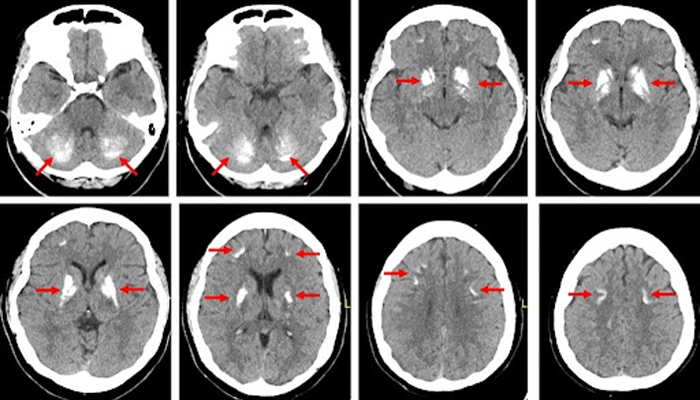

Hội chứng Fahr là tình trạng lắng đọng canxi đối xứng hai bên tại hạch nền, tiểu não và vùng chất trắng dưới vỏ não

Hội chứng Fahr thường được phát hiện tình cờ khi chụp CT hoặc MRI não do lý do khác. Tuy nhiên, để chẩn đoán chính xác, bác sĩ sẽ dựa trên lâm sàng kết hợp xét nghiệm hình ảnh và sinh hóa.

4.1. Chẩn đoán hình ảnh:

Chụp CT não: là tiêu chuẩn vàng, giúp nhìn rõ vùng vôi hóa đối xứng ở hạch nền, đồi thị, tiểu não.

MRI não: phát hiện tổn thương mô não mềm và đánh giá ảnh hưởng chức năng.

Tuy nhiên, chỉ hội chứng Fahr mới có vôi hóa đối xứng đặc trưng trên phim chụp.